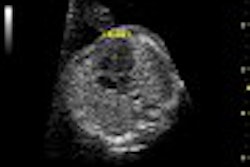

Diagnostic imaging, including echocardiography and cardiovascular MR, plays a key role in identifying abnormalities and assessing their severity to help cardiologists make clinical decisions about how to manage these issues, according to the group.

The guidelines address the lifelong surveillance of patients with repaired TOF, using a comprehensive multimodality approach without making specific recommendations for therapy. The aims of the document are to describe the role of each diagnostic modality in the care of patients with repaired TOF, and to provide guidelines for a multimodality approach that takes into account various patient- and modality-related considerations.